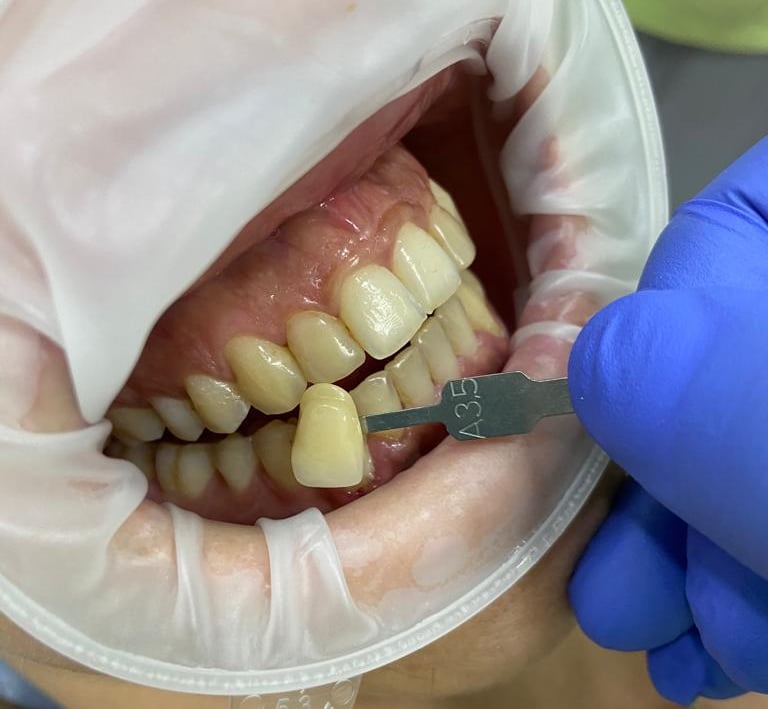

NUESTROS CASOS REALES